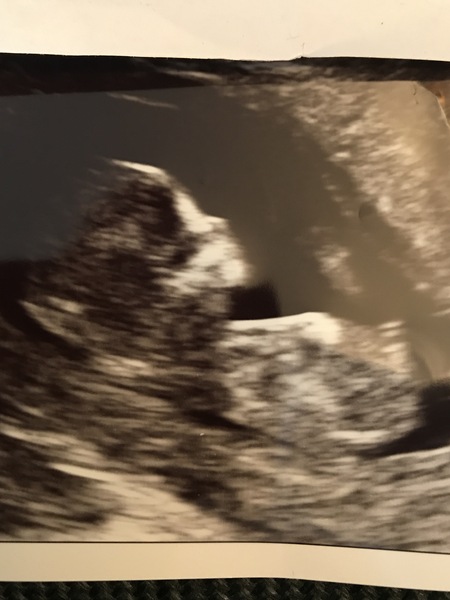

Not had a chance to catch up since yesterday morning - chatterboxes! - but popping on to post a very baby-shaped scan pic from this morning! Everything was fine and little bubba was going nuts, rolling over, bunny hopping it's little legs, stretching. Had my dates changed to a week later than I thought too so am now 12+5 and due in November...but don't kick me out Grin

I've got to wait a week for the Harmony results to come back but the sonographer said based on the nuchal fold I looked low risk. Hoping she wouldn't say that if she wasn't sure!

pause!! That's a lovely scan pic ♥️ congrats on making a baby-shaped baby and for being a week closer to meeting them 😁 how exciting!!

Pauseplayrepeat congratulations!!!! And you skipped a week ahead you lucky thing! A fantastic picture.

What an amazing scan picture! Proper little baby Smile

Awww hello to our first Blob to Baby @pauseplayrepeat, gorgeous Grin

Oh Pause ! That's so lovely Smile

Lovely scan Pause!!